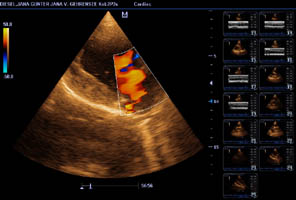

Herzultraschall von Lena vom Gehrensee zur Vermeidung von DCM

Durch Klick auf die Übersicht können die Herzdaten eingesehen werden.

Der Herzcheck ergab keinen Hinweis auf DCM.